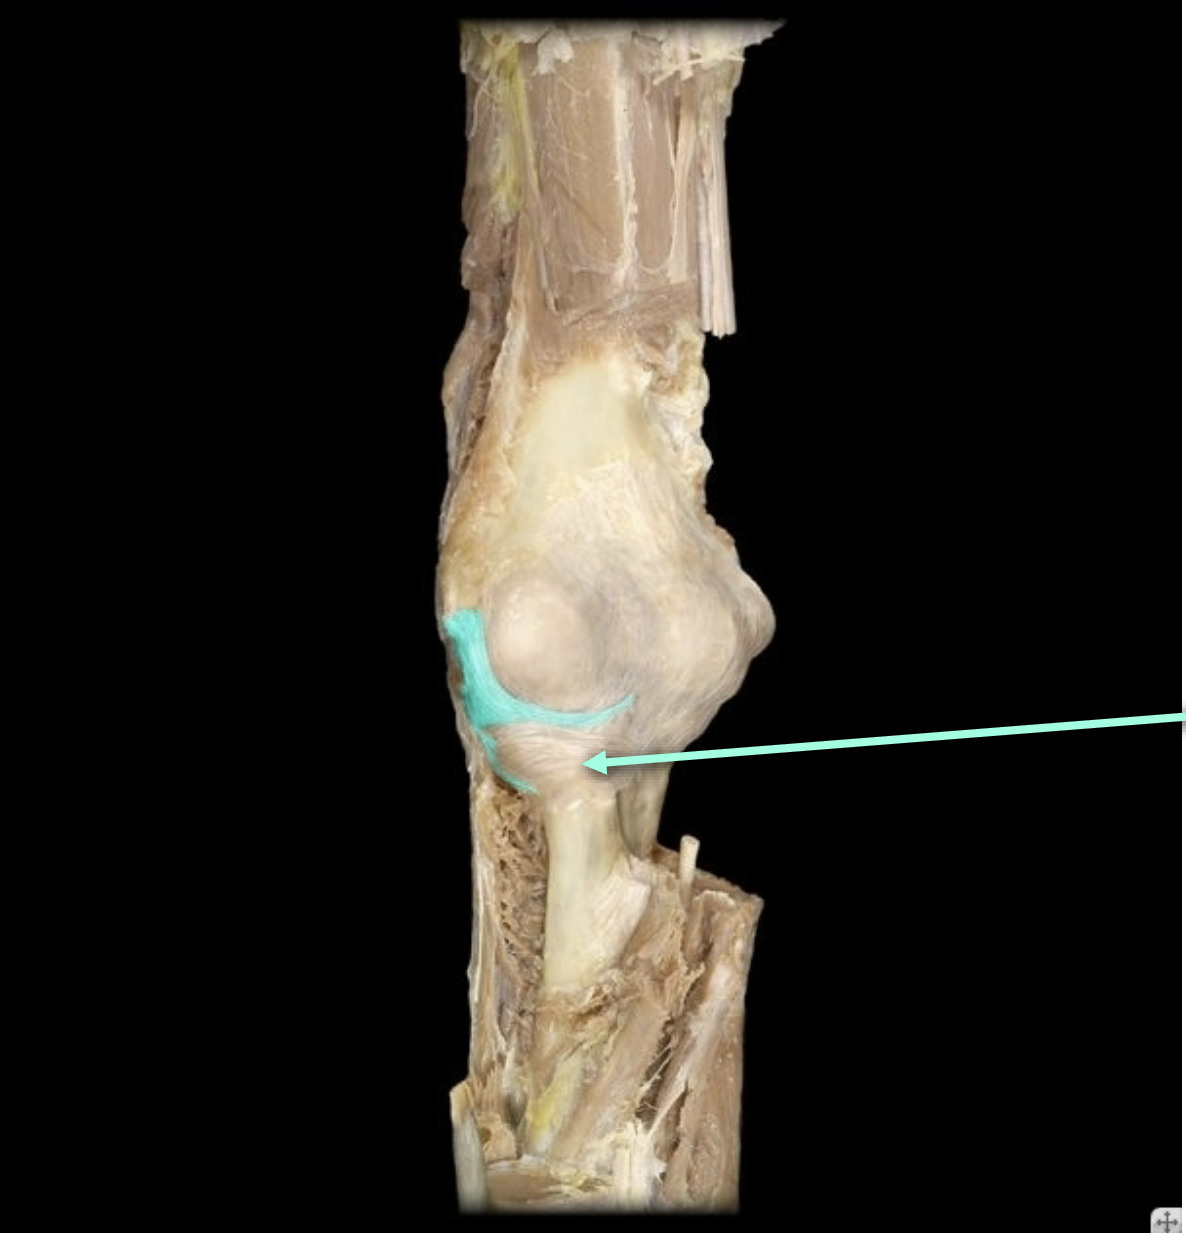

Lateral Collateral Ligament

Medial Collateral Ligament

Medial collateral ligament

Medial meniscus